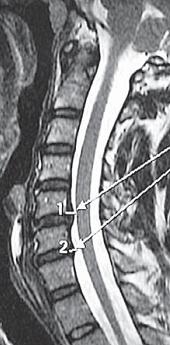

На МРТ № 18 наблюдаются грыжи межпозвонковых дисков в сегментах: — LIV-LV вентральной локализации с образованием каудального секвестра; при расположении межпозвонковой грыжи на один сегмент выше, «конфликт» с брюшной аортой был бы неизбежен; — LV-SI — дорсальная грыжа межпозвонкового диска, частично компенсированная спондилёзом МРТ № 19 ![]() МРТ № 20 ![]() На МРТ № 19 наблюдается дорсальная грыжа межпозвонкового диска шейного отдела позвоночника в сегменте СV-СVI с компрессией спинного мозга На МРТ № 20 наблюдается грыжа межпозвонкового диска шейного отдела позвоночника в сегменте CV—CVI и протрузия в сегменте CVI-CVII Замечу, что если грыжа межпозвонкового диска имеет достаточно большой размер и локализована в шейном отделе, то она способна вызвать не только соматические нарушения, но и даже психические расстройства. Причина кроется в сдавлении дурального мешка грыжей межпозвонкового диска (дуральный мешок — это герметичный соединительнотканный мешок, формируемый твёрдой мозговой оболочкой, в котором расположен спинной мозг). Как известно, спинной мозг не имеет болевых рецепторов. Однако вышеуказанная патология приводит к локальному устойчивому возбуждению определённых зон коры головного мозга. На субъективном уровне это может проявляться как постоянное чувство тревоги (так называемый «синдром ожидания»). Грыжи межпозвонковых дисков в грудном отделе позвоночника явление довольно редкое, но всё же наиболее опасное. Опасное потому, что эпидуральное пространство в грудном отделе позвоночника узкое по сравнению с другими отделами, в пределах всего 0,2–0,4 см по всей окружности дурального мешка (твёрдой оболочки спинного мозга). Поэтому даже небольшое грыжевое выпячивание может сдавить спинной мозг и вызвать тяжелейшие осложнения. Но, как уже говорилось, это явление в грудном отделе позвоночника редкое, поскольку высота межпозвонковых дисков довольно мала, всего около 3–5 мм, да и грудной отдел позвоночника менее подвижен по сравнению с другими отделами за счёт жёсткого рёберного каркаса, а значит, менее подвержен травматизации. МРТ № 21